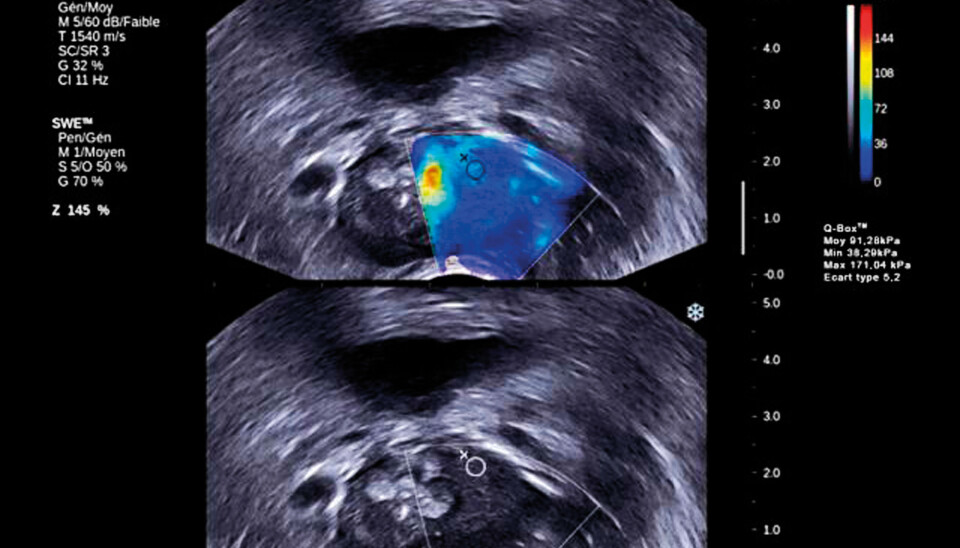

Ultrasound creates two types of waves: pressure waves and shear waves. Current ultrasound examinations measure the pressure waves. The new ultra sound examination measures the shear waves. Until now it has not been possible to measure the shear waves. Shear waves can be used to measure elasticity in soft tissue. (Photo: Supersonic Imagine)

Ultrasound creates two types of waves. The most common type is pressure waves. Pressure waves go down into the tissue. The other waves are created by the radiation pressure from pressure waves and run horizontally. These waves are called shear waves.

While pressure waves are mostly affected by fluids, the shear waves capture the characteristics of the other 30 per cent of the body that does not consist of water.

"We study how the shear waves behave in the tissue, and look at viscosity (studies how liquid the fluid is), attenuation and velocity", says Holm.

Shear waves are created when pressure waves are sent to specific points. From there, the special diagonal energy waves are created. The trick is to use the regular ultrasound waves to measure the diagonal energy pulse.

"We must reconstruct what happens. We must discard all information from the pressure waves and only retain the information from the shear waves", says Holm.

The pressure wave has a speed of 1,500 metres a second. The shear wave has a speed of one to ten metres a second.